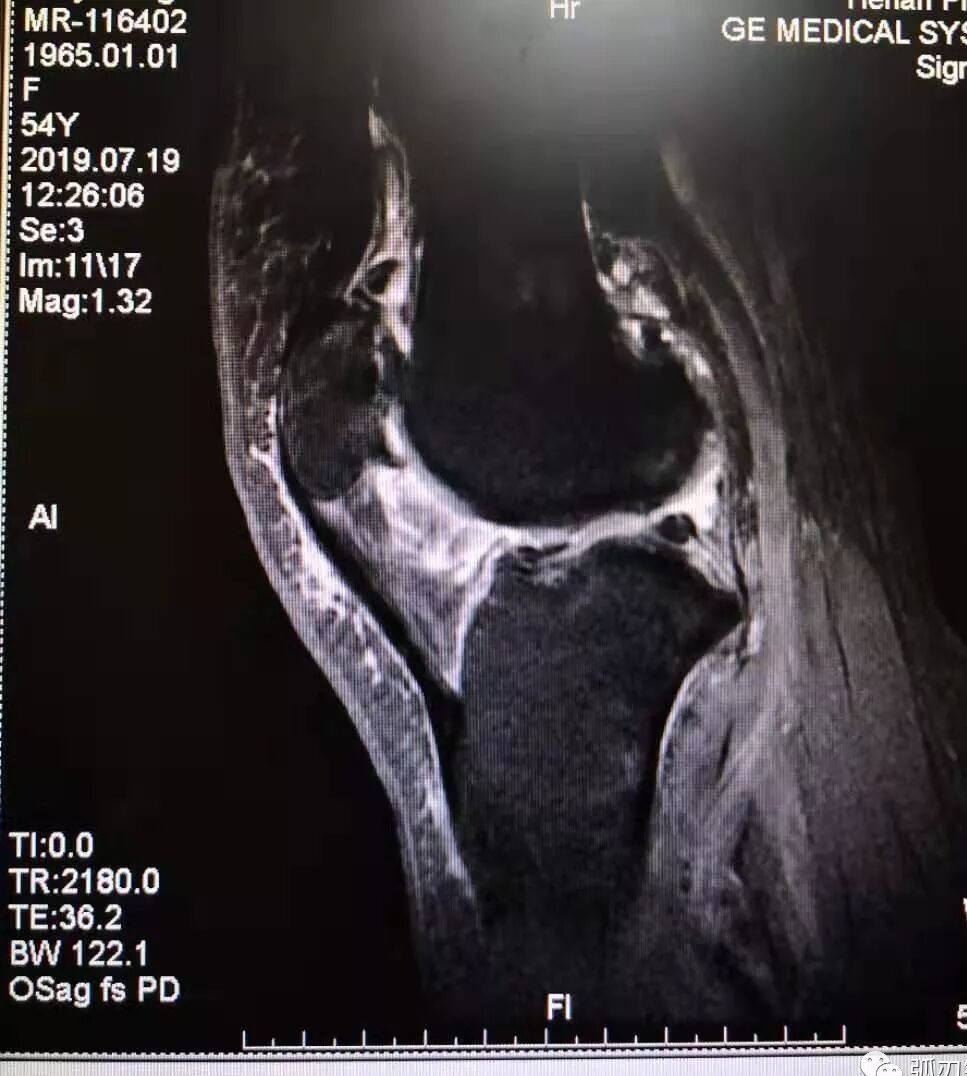

膝关节骨关节炎的磁共振影像

一例弧刃针标准疗法治膝关节骨关节炎的典型病例